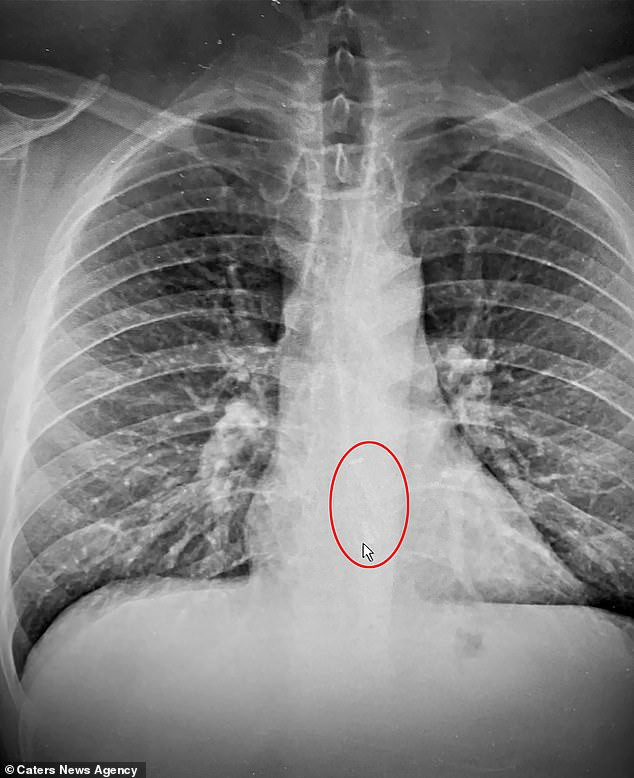

Ngày 2/2, Brad Gauthier đột ngột nôn khan chỉ vì uống một cốc nước sau khi rời giường. Chẳng biết mình bị làm sao, người đàn ông 38 tuổi ở thành phố Worcester, bang Massachusetts (Mỹ) đến bệnh viện khám thì được thông báo tin "sét đánh ngang tai". Kết quả chụp X-quang cho thấy một bên tai nghe Airpod của anh bị mắc kẹt trong thực quản!

Khi nghe Gauthier trình bày về tình trạng của mình, các bác sĩ cho rằng anh khó chịu do những món ăn trong bữa tiệc sinh nhật vợ vào đêm trước. Ngờ đâu, kết quả chụp X-quang lại vạch trần "thủ phạm" thật sự là chiếc tai nghe yêu quý mà anh đeo trong lúc ngủ.

Kết quả chụp X-quang lại vạch trần 'thủ phạm' thật sự là chiếc tai nghe yêu quý mà anh đeo trong lúc ngủ.

Người đàn ông 38 tuổi tin rằng chiếc Airpod đã vô tình rơi vào miệng và bị anh nuốt xuống trong lúc ngủ. May mắn thay, nó không kẹt lại ở vị trí hung hiểm nào. "Nếu nó chắn ngang đường thở của tôi thì vấn đề sẽ nghiêm trọng hơn nhiều. Số tôi rất may khi mọi chuyện được giải quyết cực kỳ nhanh chóng", anh cho biết.